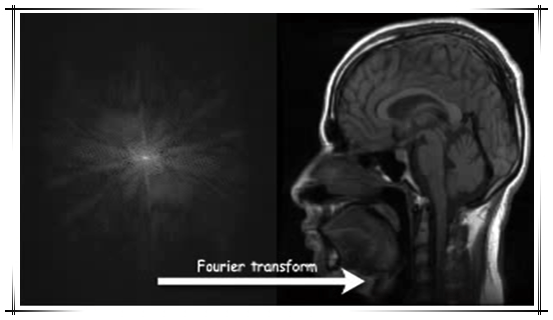

傅里叶变换就是将信号的时间-强度函数关系转变为频率-强度的函数关系。利用XY方向上的傅里叶变化,可实现XY平面内的MR信号的空间定位,实现断面图像的重建。